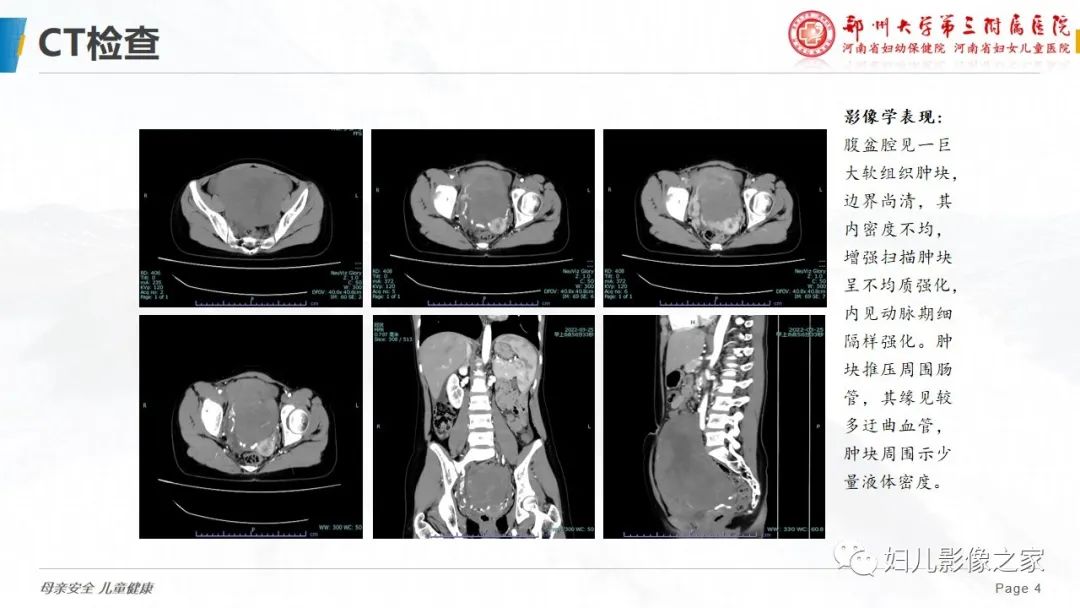

【病例】卵巢无性细胞瘤1例CT及MR影像-4